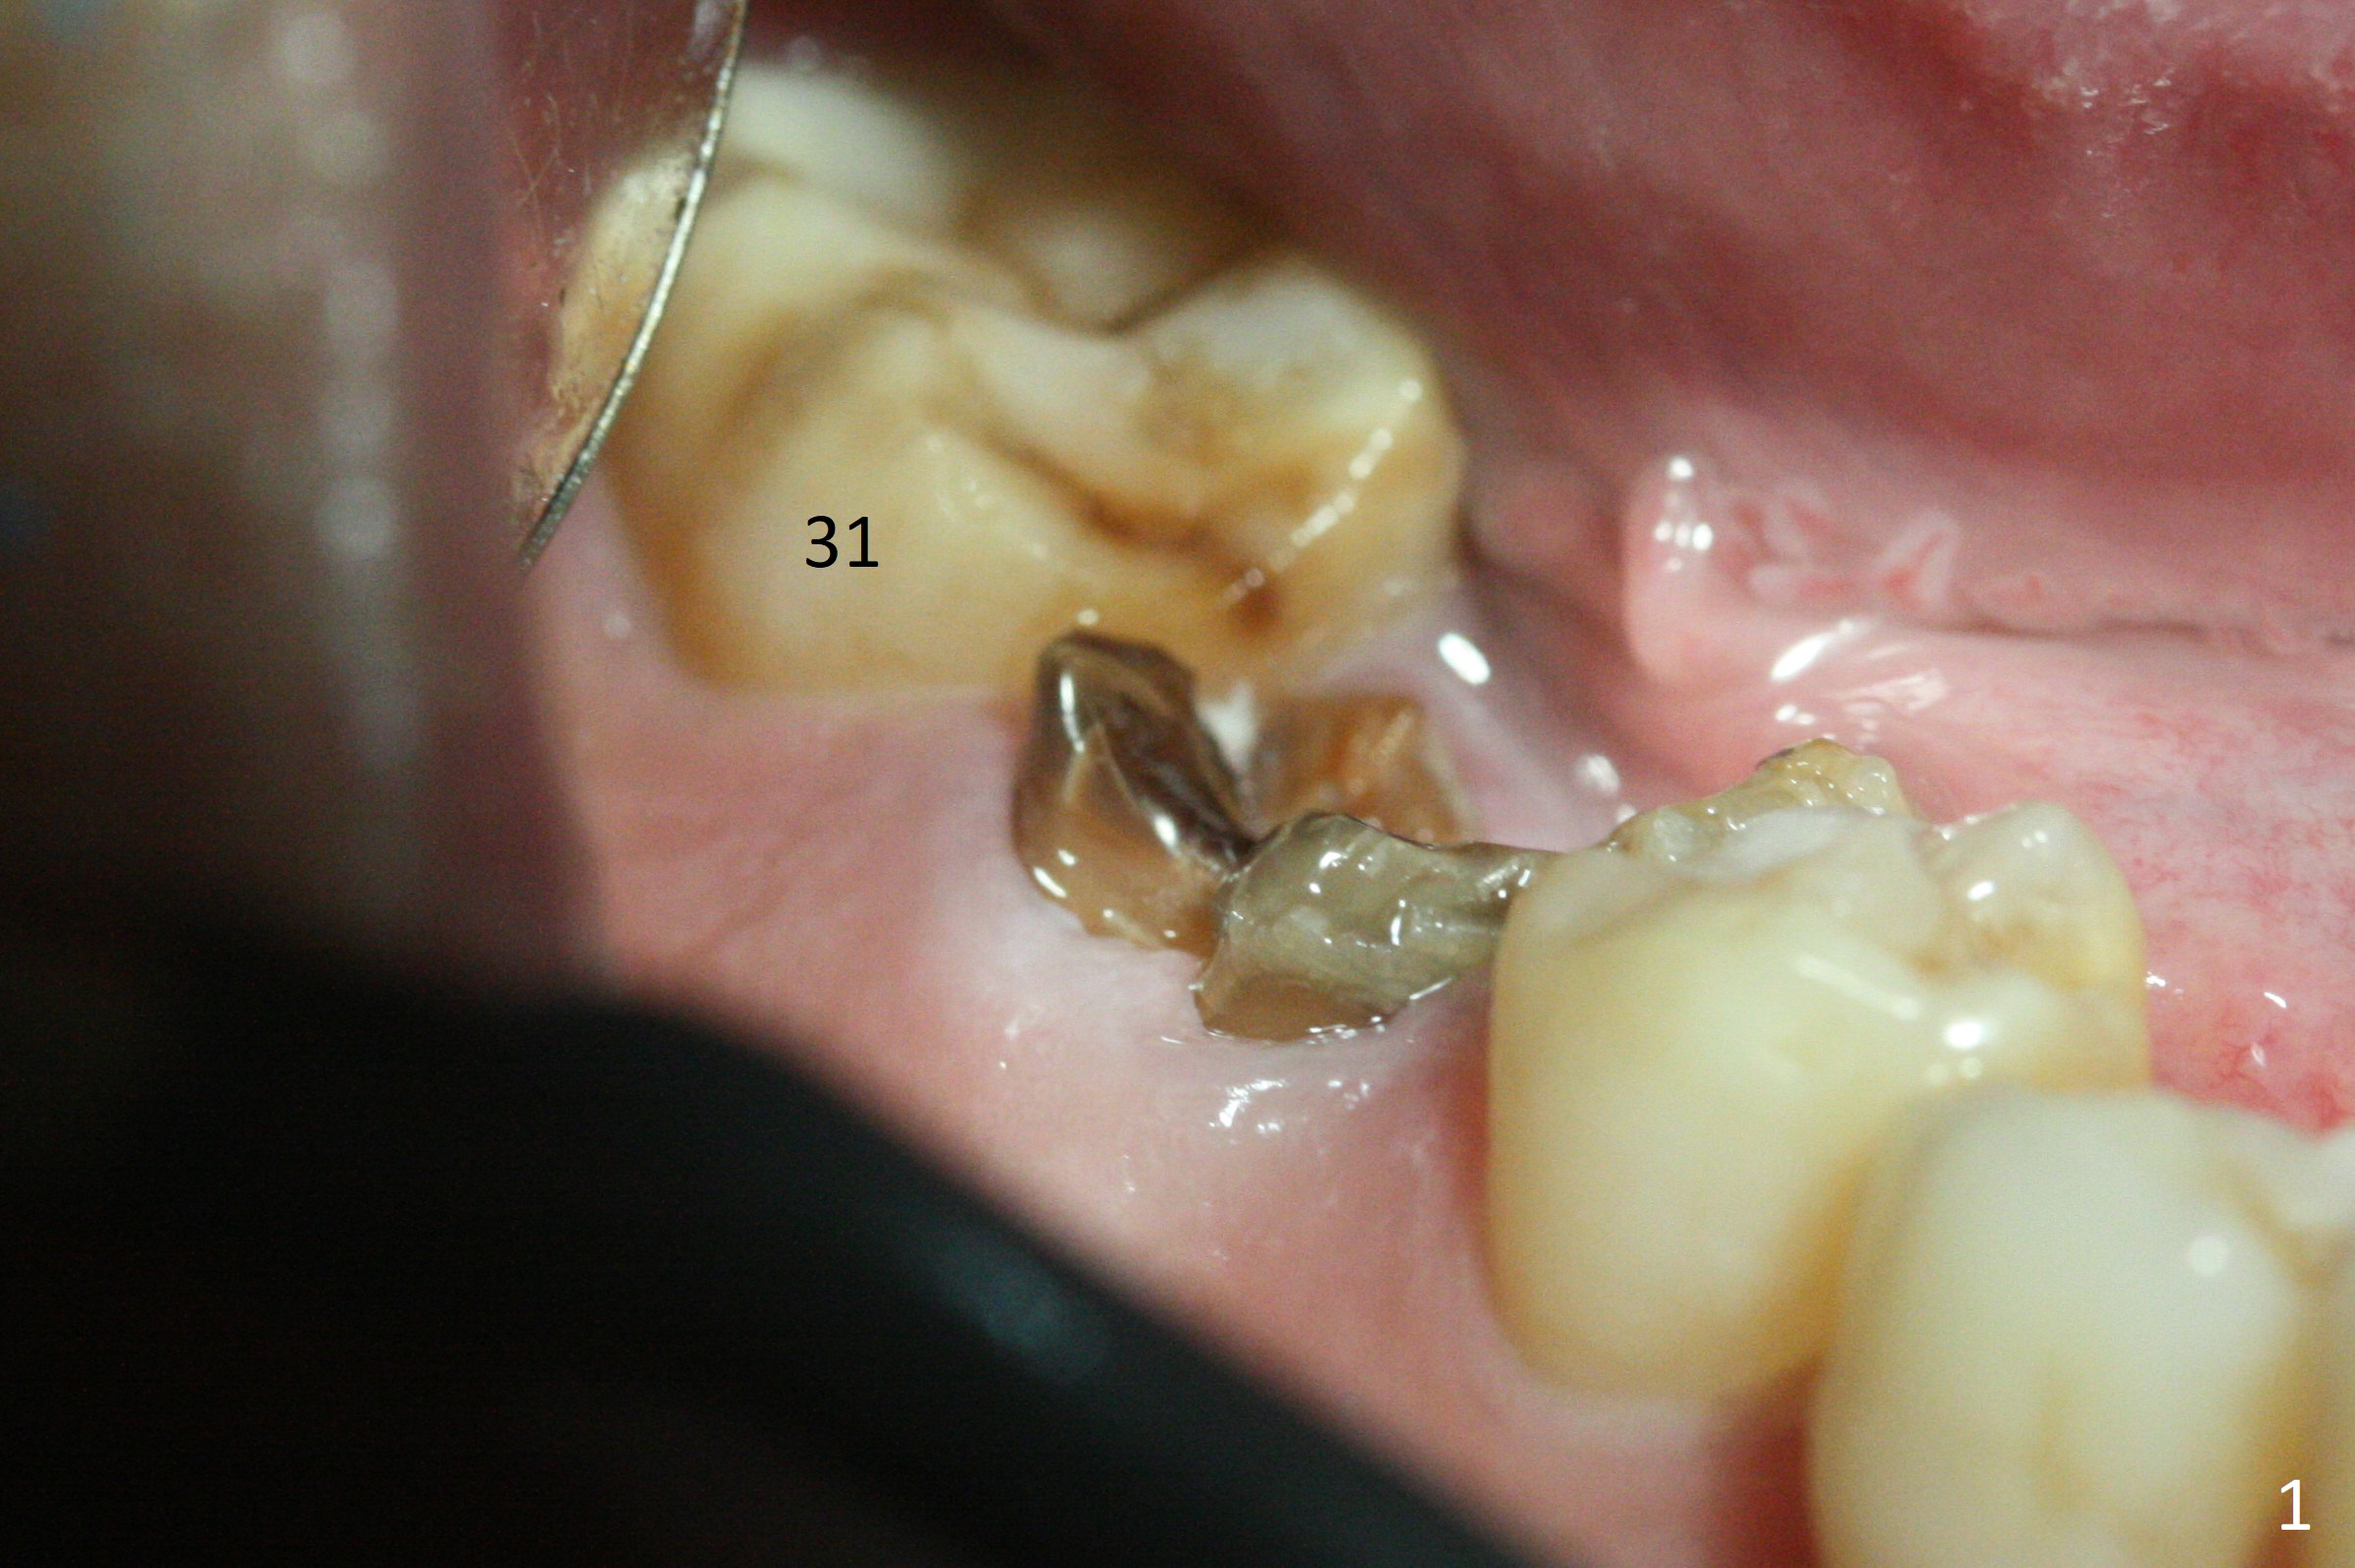

After removal of the residual roots at #30 (Fig.1), a thin septum (Fig.2 *) is removed with Rongeur (Fig.3). Following use of 4.8 mm Magic Drill, a 5x9 mm dummy implant is placed (Fig.4). To reduce socket gap (*), a 6 mm IBS implant is inserted with >50 Ncm (Fig.5). What is unexpected is heavy reduction in the height of a 6.5x4(3) mm abutment (A) because of the short crown height of the lower posterior teeth (Fig.1) and supraeruption of the tooth #3. The immediate provisional is unstable postop. The remade one dislodges soon, so does the abutment (Fig.6, 3 months postop). It appears that bone pattern in the distal socket changes.